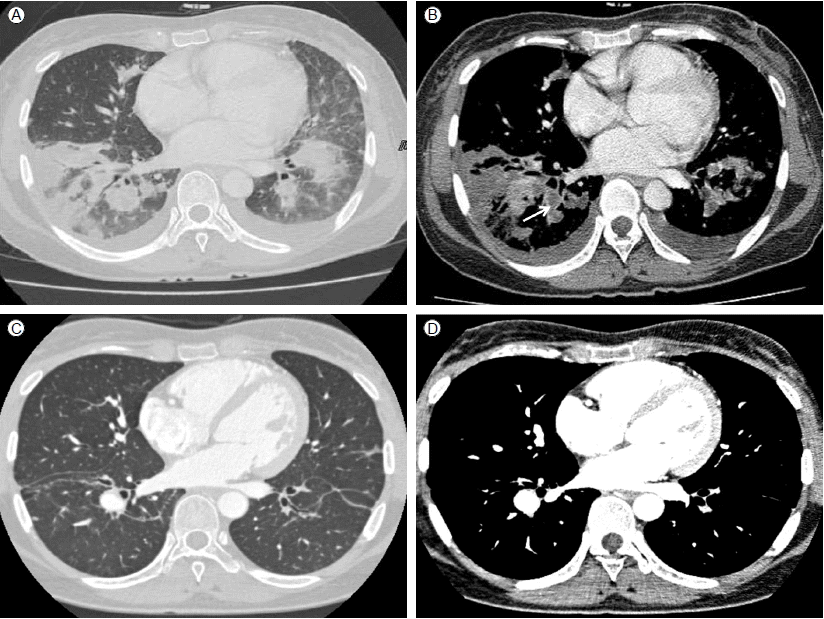

입원 6일(진균혈증 발생 22일)째까지도 39℃ 이상 열이 지속되어 흉부, 복부 컴퓨터단층촬영술(CT)을 시행하였다. 흉부 CT에서 양측 폐야에 다발성 결절 음영이 있고 기관지 주위 반점형 경화성 병변(peribronchial patchy consolidation) 및 젖빛유리혼탁(ground glass opacity), 간질비후(interstitial thickening)가 관찰되었으며 우하분엽 폐동맥과 그 하방 및 좌하엽 폐 동맥과 그 하방으로 거의 폐 동맥의 내강 대부분을 차지하는 다발성 혈전 색전증도 관찰되었다(Fig. 1A). 입원 7일(진균혈증 발생 23일)째 경흉부 심장초음파 추적검사에서 0.1 × 1.25 cm, 0.18 × 0.82 cm의 진동하는 에코 발생 종괴(oscillating echogenic material) 2개가 우심방의 상대정맥 삽입부에서 관찰되었다(Fig. 2).

Figure 1.

Chest CT showed deep vein thrombosis on admission and after discharge: Multiple peripheral nodular lesions and peribronchial patchy consolidations with ground glass opacities are seen on both lobes on admission day 6 (A). Both lower lobar pulmonary arteries show massive thromboembolism (arrow) (B) and the follow-up CT angiography shows improvement (D). Parenchymal pulmonary infiltrations also show improvement in the follow-up CT after discharge (C).

폐 혈전색전증의 정확한 평가를 위해 심부 정맥 혈전 컴퓨터단층촬영(DVT-CT)을 시행하였으며 폐동맥 혈전이 우하엽 폐동맥과 그 하방 그리고 좌하엽 폐동맥과 그 하방으로 확인되었다(Fig. 1B). 입원 22일(진균혈증 발생 38일)째 추적 관찰한 DVT-CT에서는 이전과 비교하여 양측 폐에 다발성 결절 음영과 기관지 주위 경화성 병변은 일부 호전되었으며 양측 폐동맥 혈전 색전은 조금 감소하였으나 여전히 남아있었다.

Amphotericin B 25일간 총 누적용량 1,290 mg 투여 후 흉부 단층 촬영을 시행하였으며 다발성 결절 음영과 기관지 주위 반점형 경화 병변의 호전 소견 보여(Fig. 1C) fluconazole 400 mg/day 경구 투약으로 변경하였다. 진균혈증 발생 103일 째 시행한 흉부 혈관 조영 컴퓨터단층촬영(chest CT angiography)에서 양측 하분엽 폐동맥 분지의 혈전 호전 소견이 보였다(Fig. 1D). 진균혈증 발생 109일째 안과 추적검사를 시행하였고 칸디다 내인성 안내염은 모두 호전되어 더 이상 병변은 관찰되지 않았다. 환자는 경구 fluconazole 400 mg/day 총 24주 동안 투여 후 치료를 종료하였다.

Iwasaki 등[9]이 10명의 패혈성 폐 색전증 환자를 대상으로 시행한 연구에서 변연부의 다발성 결절형, 혈관의 끝에 보이는 병변(feeding vessel sign), 쐐기 모양의 결절이 패혈성 폐 색전증의 특징적인 흉부 단층촬영 소견임을 확인하였는데 본 증례의 환자에서도 흉부 단층 촬영상에서 양 폐야의 주변에 다수의 결절형이 확인되었다. 또한 기관지 주위 반점형 경화성 병변 외에도 젖빛 유리 혼탁 현상이 있어 진균성 폐렴의 특징적인 소견을 보였다.